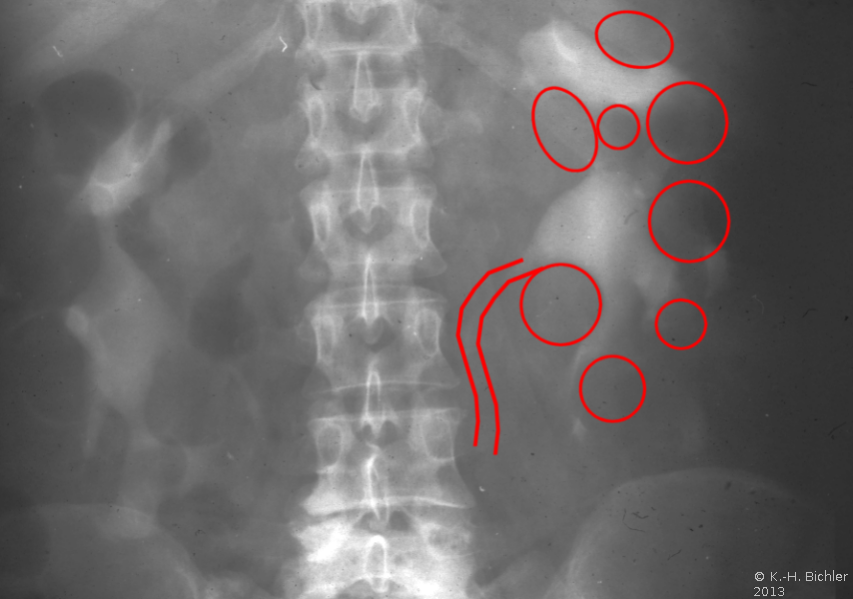

Die Diagnose wird mittels Anamnese (zystische Nierenerkrankungen in der Familie), RR-Messung, Labor (Kreatinin) mit genetischer Untersuchung, Sonographie, Computertomographie und gegebenfalls Kernspintomographie gestellt (Abbildung 4).

Ein i.v.-Pyelogramm kann im Rahmen der differentialdiagnostischen Abklärung des Flankenschmerzes indiziert sein (Abbildung). Sofern schon eine ausgeprägte Niereninsuffizienz vorliegt, sollte die Abklärung mit einem retrograden Pyelogramm erfolgen (Abbildung 5).